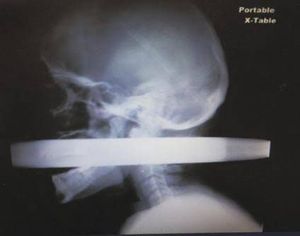

This X-ray shows 28-year-old Las Vegas man Andrew Linn, who survived a 2010 car accident that pushed a 2-inch-thick metal fence pole through his mouth and out through the back of his neck, according to a report of his case in the Las Vegas Review-Journal.

Linn "was very calm and didn't appear in any pain," surgeon Dr. Jay Coates, of University Medical Center, told the Review-Journal. The medical team at was able to remove the pole without damaging either of two major blood vessels — the carotid artery and jugular vein — in the neck region.